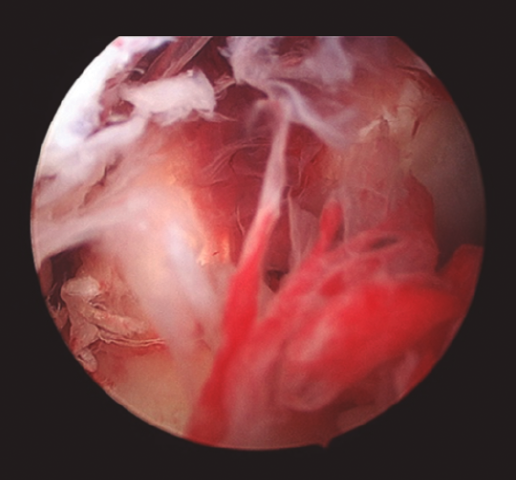

Figura 3. Imagen intraoperatoria artroscópica que muestra el abundante tejido esfacelar en un caso de artritis séptica de rodilla.

Cuando la infección ya se ha producido, el tratamiento de elección debe ser realizado tan pronto como sea posible y en cuanto haya sospecha clínica de infección, refrendada o no por los resultados de las pruebas complementarias, los cuales no justifican una demora en la actuación. Este tratamiento consiste en asociar un desbridamiento artroscópico agresivo al inicio del tratamiento antibiótico(4,5,9). Durante el desbridamiento artroscópico es obligatorio recoger muestras para el cultivo antes de la administración de antibióticos, y ambas terapias deben realizarse lo antes posible. La artroscopia debe incluir lavado extensivo con suero, desbridamiento de tejido desvitalizado, eliminación de fibrina, coágulos y sinovectomía (Figuras 3 y 4).